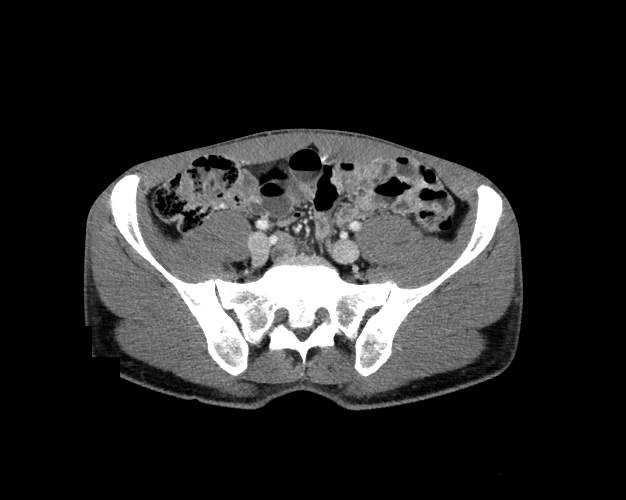

Body

Covers abdominal CT anatomy.